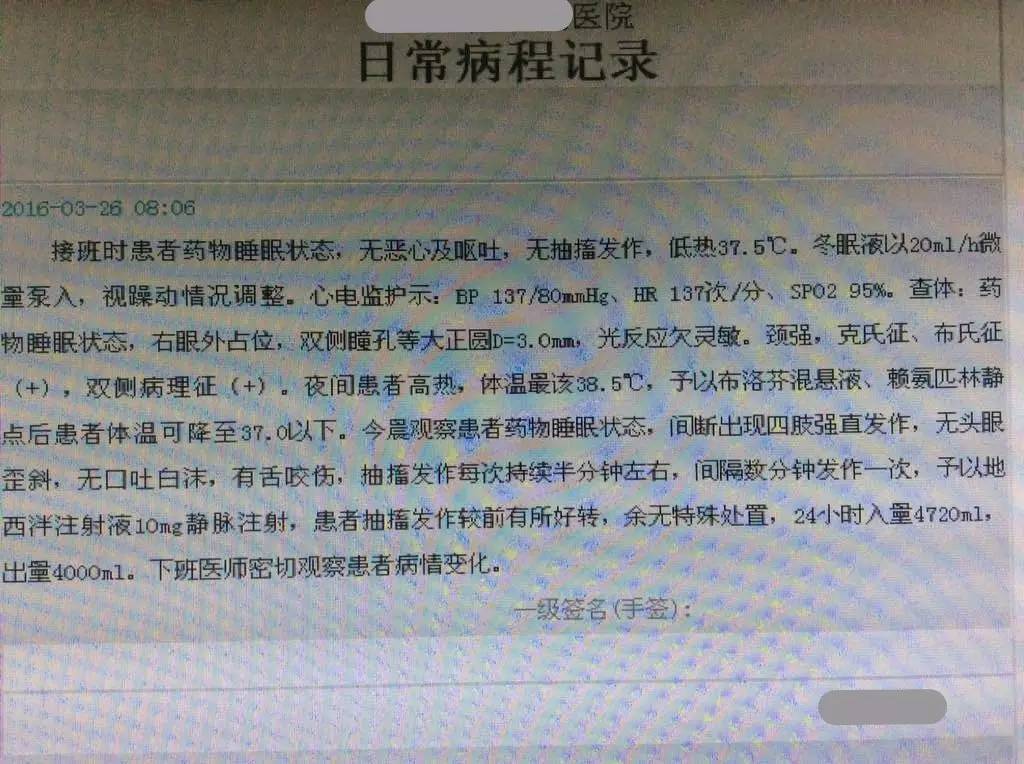

现病史:患者于入院1天前无明显诱因由家属发现头痛,头痛性质及部位不能提供,家属诉其头痛难以耐受,伴恶心、未呕吐,随后逐渐出现烦躁不安、胡言乱语等情况,不能听懂及理解他人谈话内容,无肢体活动不灵,无意识丧失及二便失禁,未予以重视,患者上述症状持续无缓解。入院6小时前患者无明显诱因出现发作性肢体抽搐,家属诉当时患者意识不清,双上肢屈曲、双下肢伸直,头向左侧偏斜,双眼上视、牙关紧闭、口吐白沫、小便失禁,患者肢体抽搐持续约10分钟自行停止,抽搐发作后仍烦躁不安、胡言乱语,再发后未予以任何处置,急来我院,行头颅CT示左额叶低密度影,急诊以“头痛、精神行为异常原因待查”收入我科。患者自发病以来,精神行为异常,饮食睡眠差,大小便正常。

查体:生命体征平稳,意识模糊,双瞳孔正大等圆,光反射灵敏,余脑神经查体欠合作。四肢肌力、肌张力检查欠合作,双侧腱反射存在对称,感觉运动查体欠合作,双侧病理征(+)。颈抵抗。